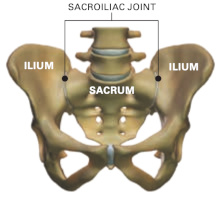

- Surgical management of pelvic primary bone tumors involving the sacroiliac joint. Sabourin M, Biau D, Babinet A, Dumaine V, Tomeno B, Anract P. Orthop Traumatol Surg Res. 2009 Jun;95(4):284-92. doi: 10.1016/j.otsr.2009.04.008. Epub 2009 May 30. PubMed PMID: 19482533.

- Fractures du Sacrum - Rappels anatomiques et classification. Sabourin M, Rousseau MA, Sofia T, Lazennec JY : In Traumatismes de la ceinture pelvienne. Sauramps Medical. 2007.pp 143-150

- Fractures en U du sacrum - Mécanisme physiopathologique et expérience de la Pitié. Sabourin M, Rousseau MA, Sofia T, Lazennec JY, Bendaya S In Traumatismes de la ceinture pelvienne. Sauramps Medical. 2007. pp 151-160